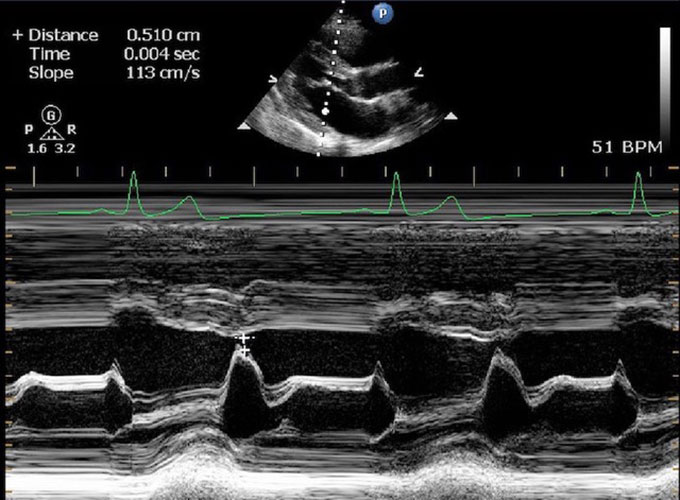

This is an echocardiogram image of an ape’s heart. The wedge shape at the top is a cross-section through the heart. The white lines show heart muscle and the black is where blood flows. A heart specialist can measure the thickness of the walls and how well the heart contracts.Courtesy of H. Murphy/Zoo Atlanta